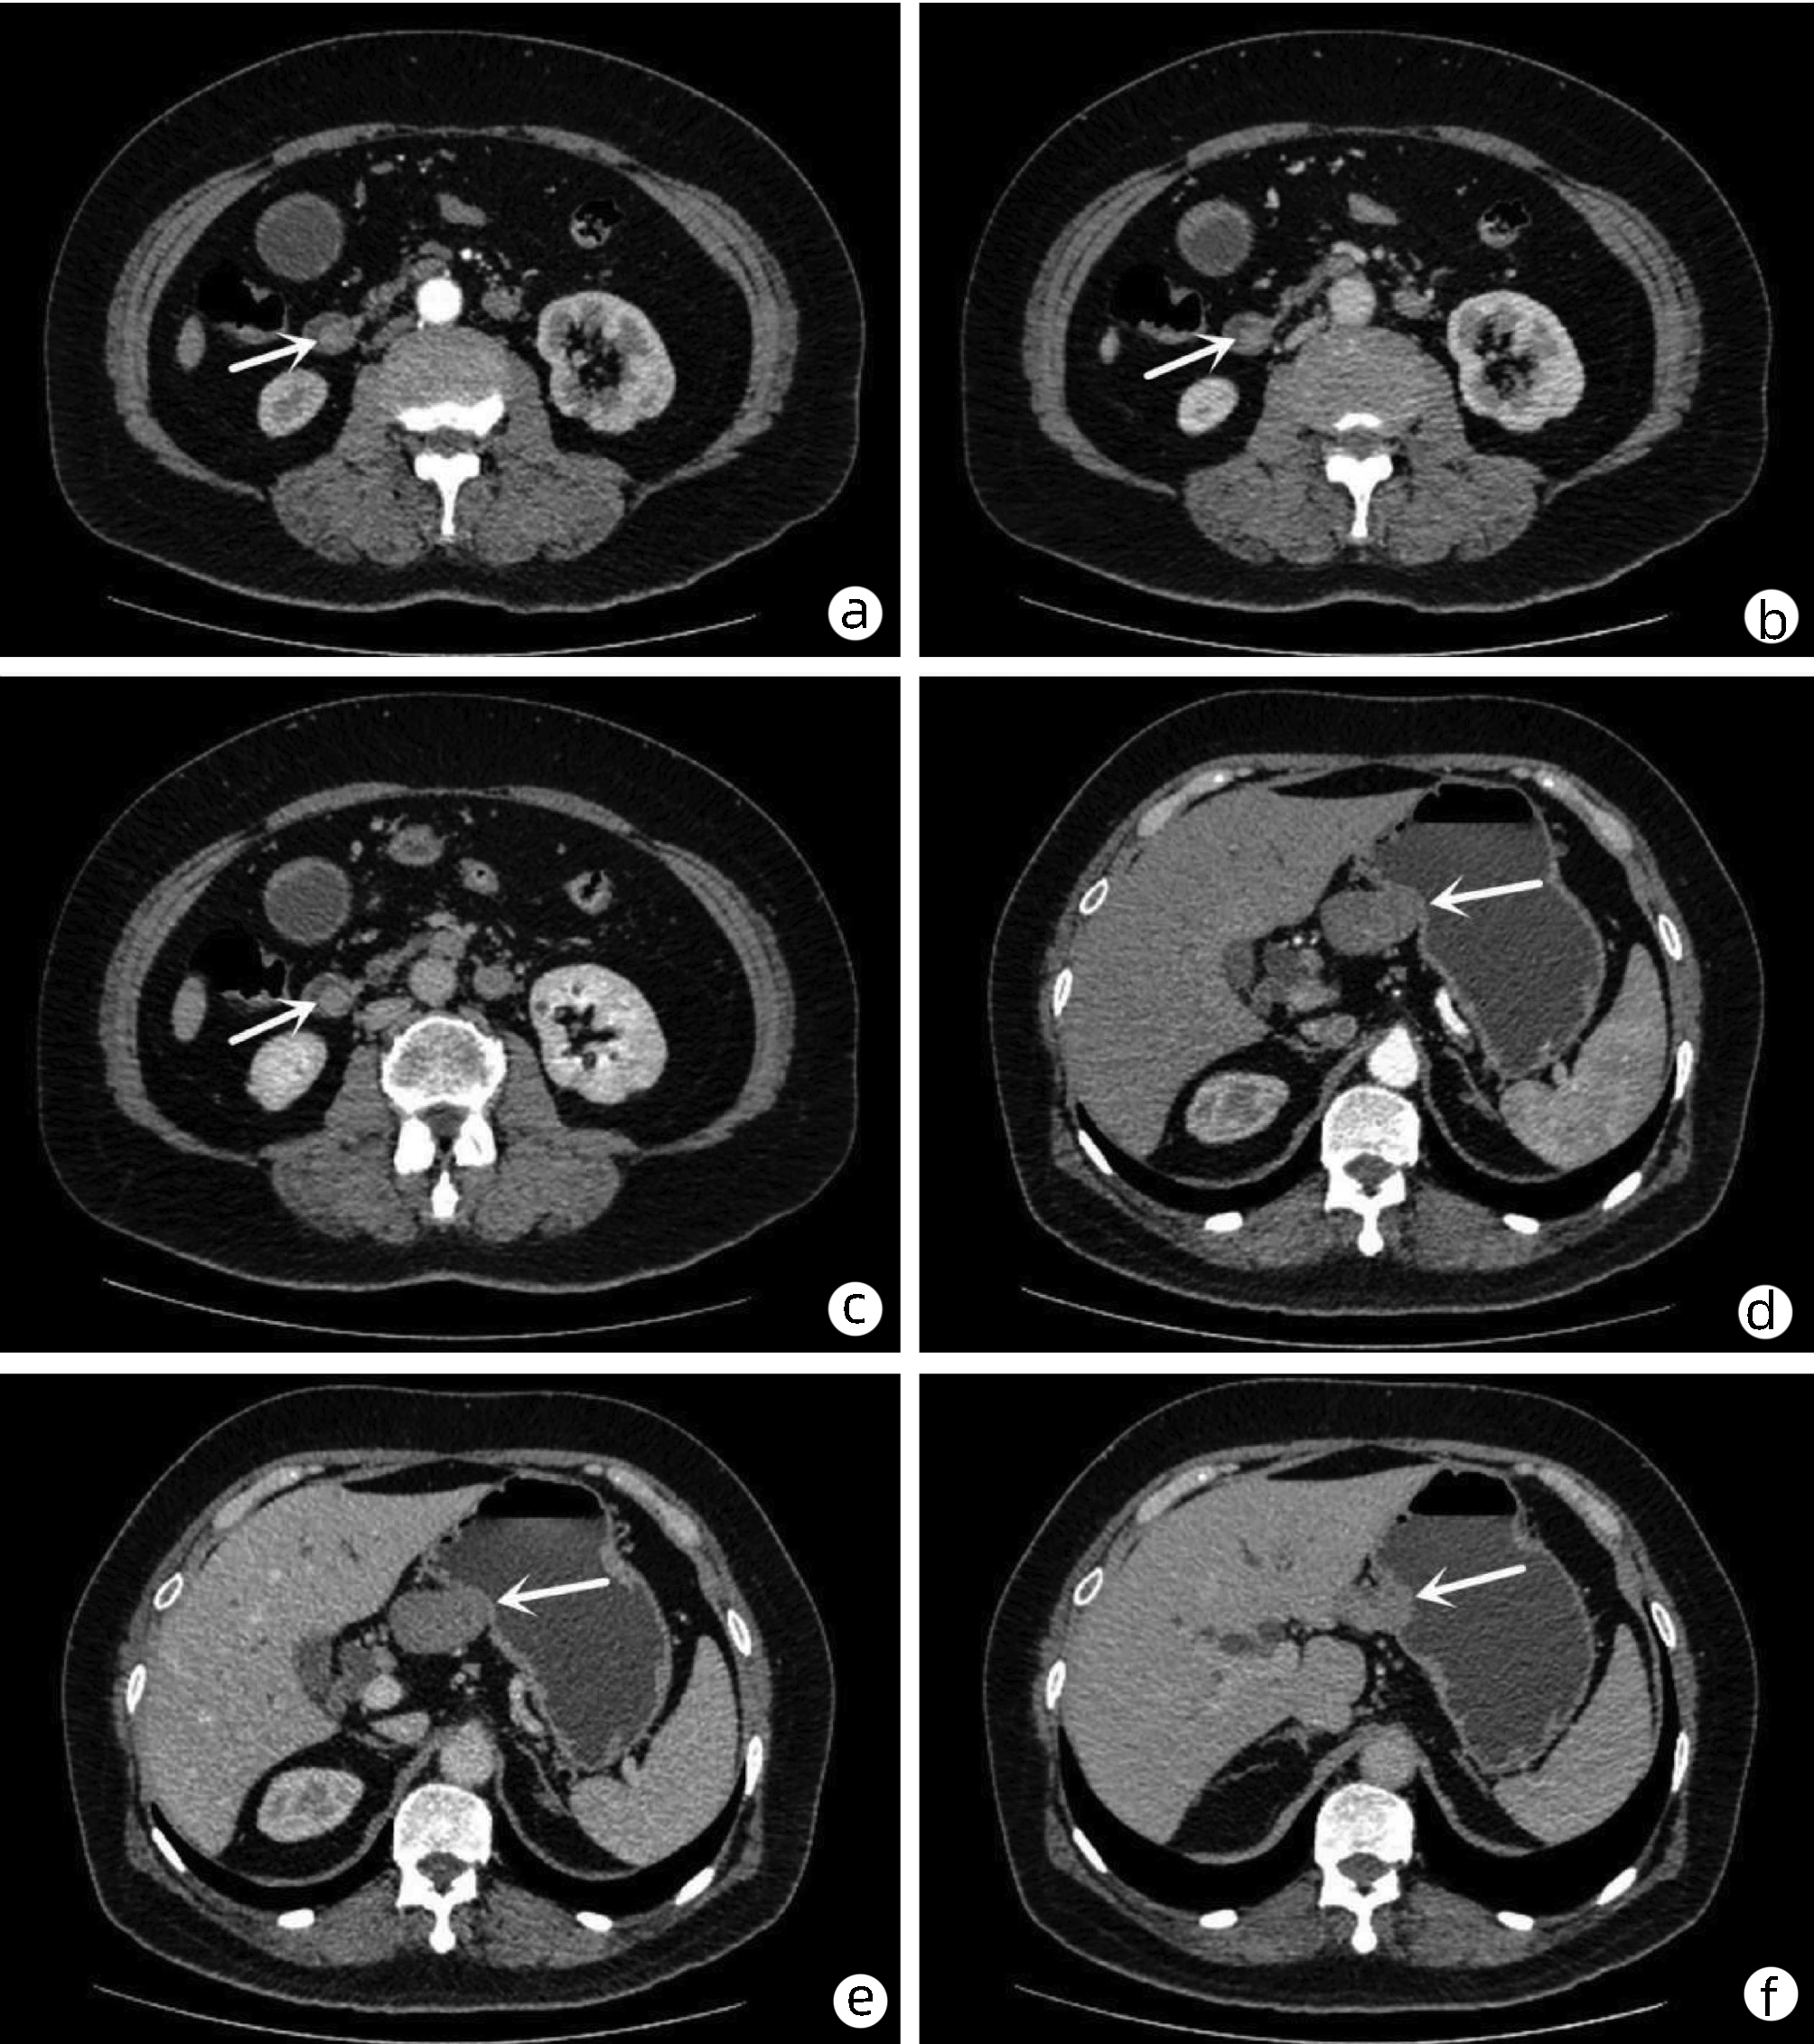

乙型肝炎肝硬化上消化道出血的ΔCT特征性表现及预测模型的建立

李俊杰, 孙岩岩, 李将宏, 郑虹

2022, 38(5): 1081-1085. DOI: 10.3969/j.issn.1001-5256.2022.05.020

摘要(1053) HTML (308) PDF (2671KB)(64)

摘要:

目的  本研究旨在寻找乙型肝炎肝硬化CT特征,建立肝硬化上消化道出血预测模型,预测出血风险。  方法  回顾性分析2015年1月—2021年6月天津市第一中心医院101例型肝炎肝硬化患者的数据,将其分为上消化道出血组(P=58)及非出血组(n=43)。比较两组间实验室检查以及强化CT检查测的平扫期、动脉期、门脉期以及静脉期的CT值,并计算各期间CT值的变化(ΔCT)。计量资料两组间的比较使用t检验或Mann-Whitney U检验;使用logistic回归分析方法,预测相关危险因素;通过计算受试者工作特征曲线下的面积评估模型辨别力,而模型校准则通过Hosmer-Lemeshow确定。在多变量logistic回归分析结果的基础上,使用Rstudio4.1.2软件的R包构建预测的列线图模型,并绘制相应的ROC曲线、校准曲线以及临床决策曲线。  结果  非出血组血清TBil、WBC、PLT水平与出血组比较,差异均有统计学意义(P值均<0.05);两组在肝-Plain、脾-P-Plain、脾-P-A ΔCT值存在统计学差异(P值均<0.05)。单因素logistic分析结果显示,白细胞(OR=0.770,95%CI:0.624~0952, P=0.016)、血小板(OR=0.979,95%CI:0.965~0.994, P=0.006)、肝脏平扫期(OR=1.142,95%CI:1.058~1.233, P=0.001)、脾脏门脉期-平扫ΔCT值(OR=0.979,95%CI:0.959~1.000, P=0.050)、脾脏门脉期-动脉期ΔCT值(OR=0.979,95%CI:0.944~0.994, P=0.015)在乙型肝炎肝硬化患者发生上消化道出血与未出血两者之间差异具有统计学意义。多因素logistic分析结果显示血小板(OR=0.968,95%CI:0.944~0.993, P=0.011)、肝脏平扫期(OR=1.148,95%CI:1.047~1.259, P=0.003)、脾脏门脉期-动脉期ΔCT值(OR=0.951,95%CI:0.908~0.995, P=0.030)为上消化道出血的独立危险因素。基于多因素logistic分析结果,构建了乙型肝炎肝硬化上消化道出血的预测模型并绘制校准曲线。该模型的受试者特征曲线下面积为0.801,cut-off值为0.433,其对应的敏感度是81.4%,特异度是77.6%。模型的校准曲线与理想曲线贴合良好。  结论  乙型肝炎肝硬化肝脏具有特殊的ΔCT变化,通过ΔCT构建的预测模型对于乙型肝炎肝硬化上消化道出血具有良好的预测能力。